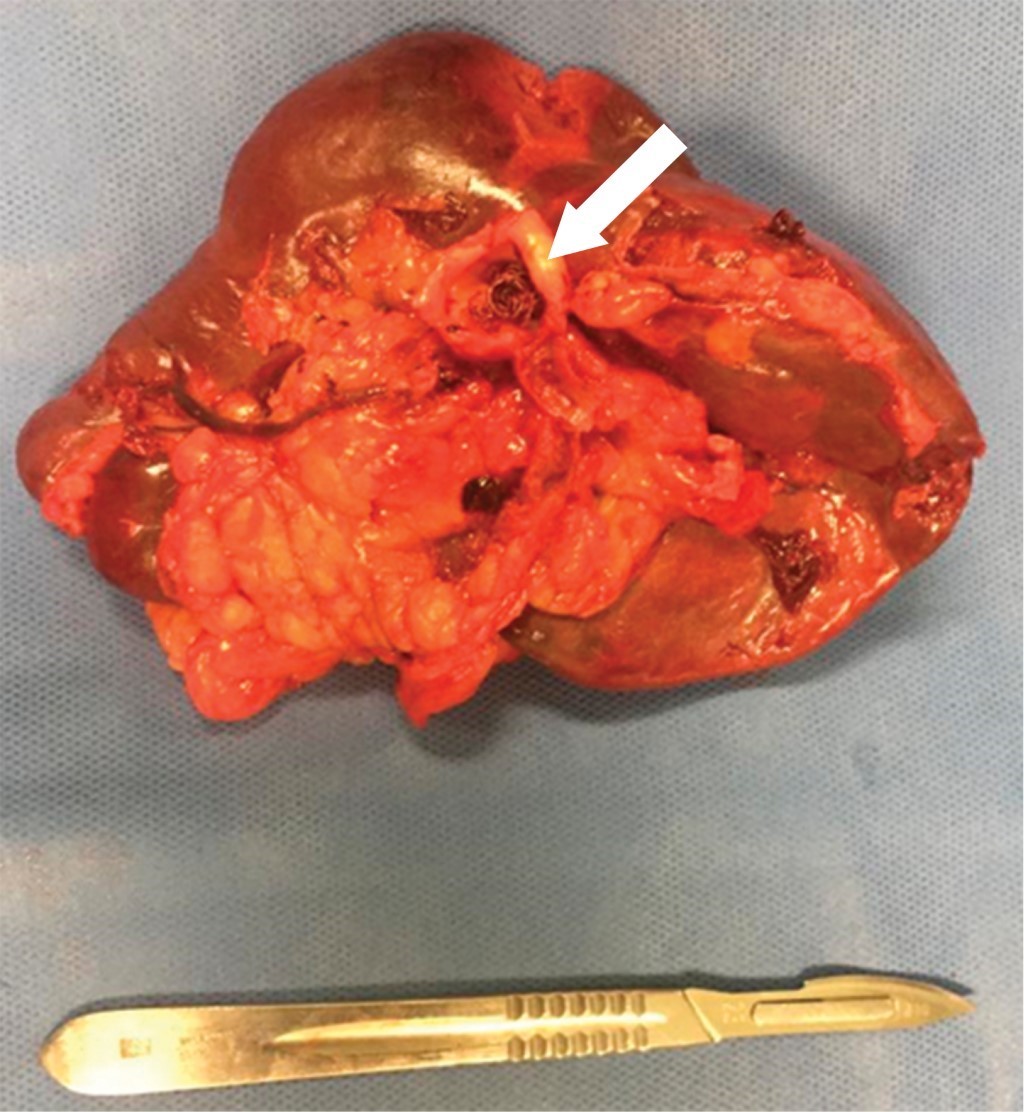

Femenino de 41 años, con antecedente de hipotiroidismo diagnosticado a los 21 años, actualmente sin tratamiento médico desde los 40 años por aparente control, diagnóstico de miomatosis uterina a los 40 años, sin tratamiento; antecedente de dos cesáreas, última a los 23 años, sin complicaciones. Accidente automovilístico con volcadura a los 40 años, sin daño orgánico aparente. Inicia padecimiento actual posterior a accidente automovilístico ocurrido un año previo con dolor en hipocondrio izquierdo, de tipo intermitente, punzante, sin irradiaciones, sin agravantes ni atenuantes; a la exploración física presenta dolor en hipocondrio izquierdo a la palpación profunda, resto sin datos patológicos. Se realizó ultrasonido con hallazgos compatibles con aneurisma de la arteria esplénica y colelitiasis, se complementa abordaje diagnóstico con angiotomografía de aorta abdominal encontrando arteria esplénica de calibre normal, con dilatación focal sacular en segmento distal compatible con aneurisma de 17.7 × 15.9 mm y cuello de 5.5 mm, con trombo mural de 2 mm, sin signos de ruptura, litiasis vesicular y miomatosis uterina. En manejo conjunto con angiología se realiza embolización selectiva con colocación de coils, sin complicaciones aparentes (Figura 1). En el seguimiento inmediato, la paciente presenta dolor abdominal y leucocitosis, se realiza nueva angiotomografía con datos sugestivos de oclusión de arteria esplénica e infarto esplénico (Figura 2). Por los hallazgos comentados se decide realizar esplenectomía y colecistectomía convencional mediante abordaje quirúrgico con incisión en línea media, supraumbilical, con los siguientes hallazgos: vesícula biliar de paredes delgadas, múltiples litos en su interior de 5-10 mm aproximadamente, arteria cística de 2 mm, conducto cístico de 3 mm, bazo de 13 × 10 cm aproximadamente, con múltiples zonas isquémicas, aneurisma de la arteria esplénica a nivel de hilio esplénico, posterior a su bifurcación (Figura 3). Cursa el postoperatorio sin complicaciones, por lo que fue egresada tres días después de la cirugía, recibió vacunación correspondiente para pacientes esplenectomizados. Reporte histopatológico con hallazgos de aneurisma de arteria esplénica con ateroesclerosis, parénquima esplénico con vasos congestivos y colecistitis crónica litiásica.

Figura 1